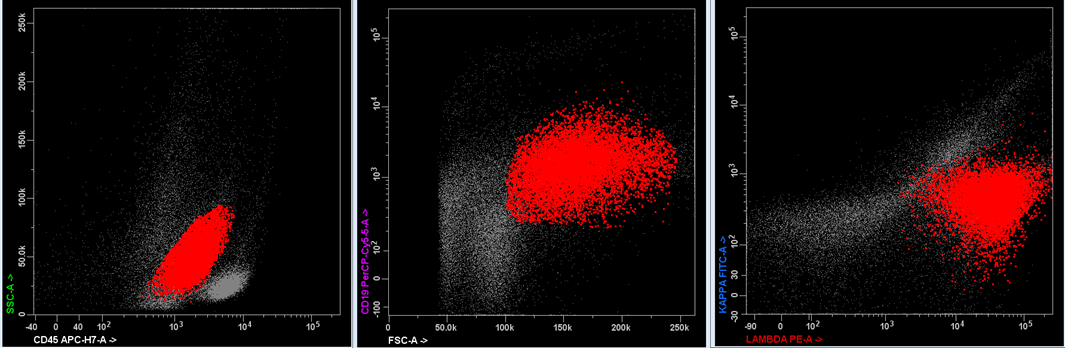

Flow cytometry description

- Flow cytometry shows a population of monoclonal B cells with high forward scatter (indicative of large size)